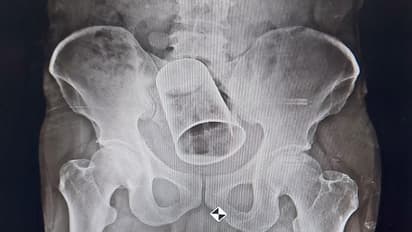

एक्स-रे रिपोर्ट में दिखा ग्लास

चेकअप के बाद डॉक्टरों ने एक्स-रे टेस्ट कराने की सलाह दी। एक्स-रे रिपोर्ट में साफ-साफ दिख रहा था कि उसके आंत में एक ग्लास है। डॉक्टरों ने पहले ग्लास को रेक्टम के रास्ते बाहर निकालने की कोशिश की, लेकिन वे सफल नहीं हुए। इसके बाद मरीज को सर्जरी कराने की सलाह दी गई।